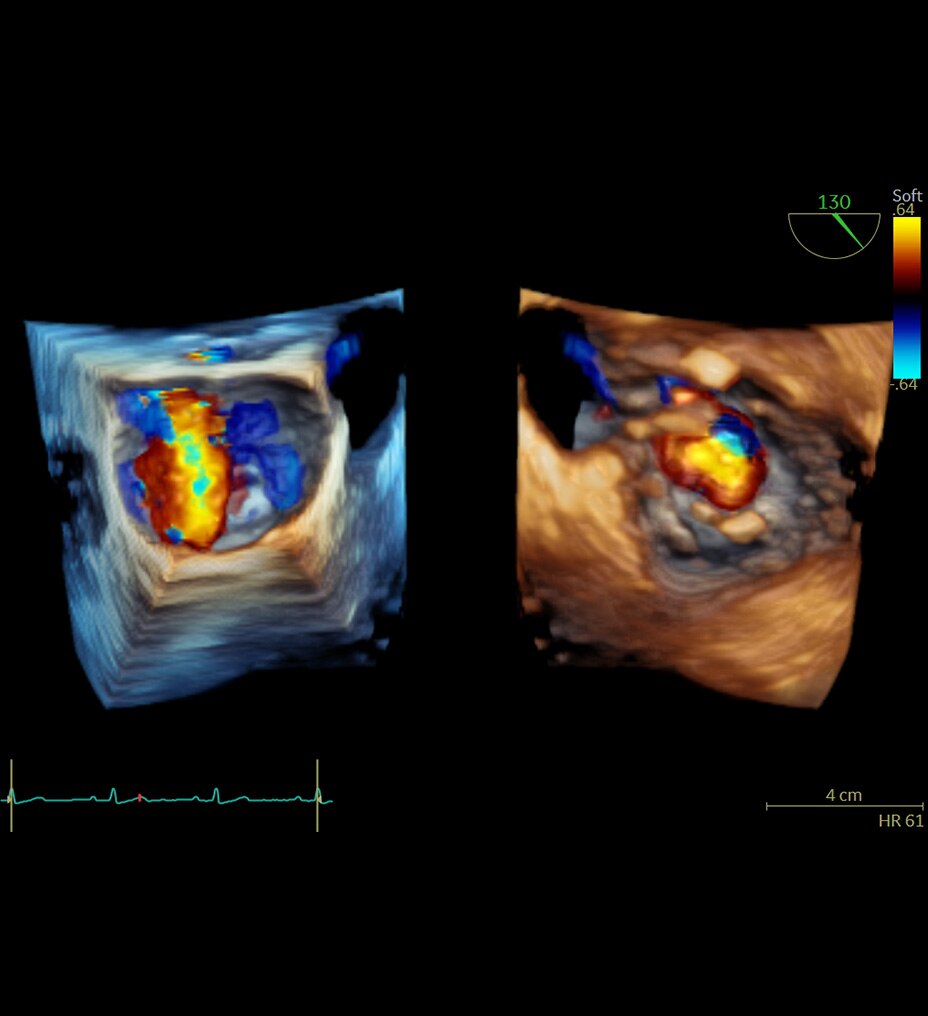

Une imagerie exceptionnelle dans un scanner IRM 1.5T à large tunnel

Une imagerie exceptionnelle dans un IRM compact 1.5 T à large tunnel

SIGNA Voyager. Utilisation prévue : est un scanner à résonance magnétique corps entier conçu pour prendre en charge la haute résolution, le rapport signal-bruit élevé, et les temps de balayage courts. Il est indiqué comme dispositif d’imagerie diagnostique pour produire des images axiales, sagittales, coronales et obliques, des images spectroscopiques, des cartes paramétriques et/ou des spectres, des images dynamiques des structures et/ou des fonctions du corps entier, y compris, mais sans s’y limiter : tête, cou, ATM, colonne vertébrale, sein, cœur, abdomen, bassin, articulations, prostate, vaisseaux sanguins et régions musculosquelettiques du corps. En fonction de la région d’intérêt à photographier, des agents de contraste peuvent être utilisés. Les images produites par SIGNA Voyager reflètent la distribution spatiale ou l’environnement moléculaire des noyaux présentant une résonance magnétique. Ces images et/ou spectres, lorsqu’ils sont interprétés par un médecin qualifié, fournissent des informations susceptibles de faciliter le diagnostic.